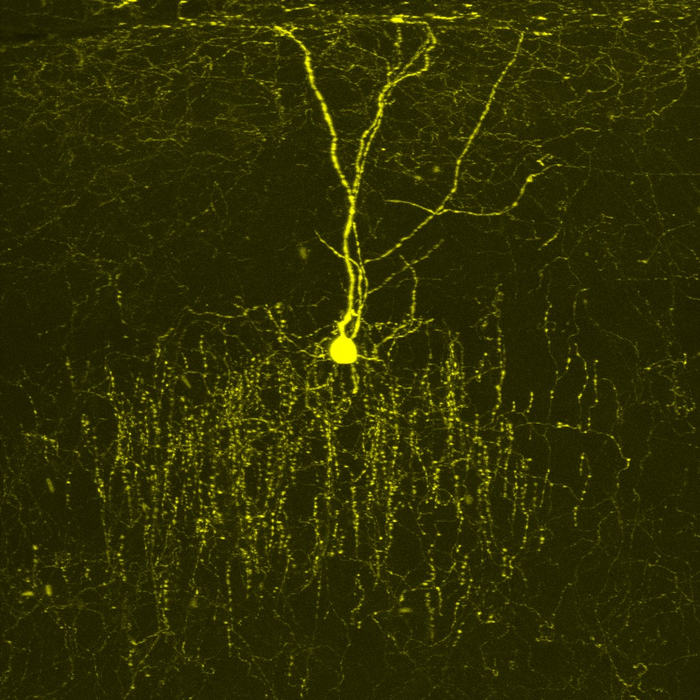

小鼠大脑皮层中被称为枝状吊灯细胞(chandelier cell )的抑制性神经元。这种细胞将树突(输入装置)发送到大脑皮层的表面,轴突(输出装置)发送到大脑皮层的内部。Liu等人报道,唐氏综合症小鼠模型中DSCAM基因的额外拷贝增加了吊灯细胞轴突末端的数量。